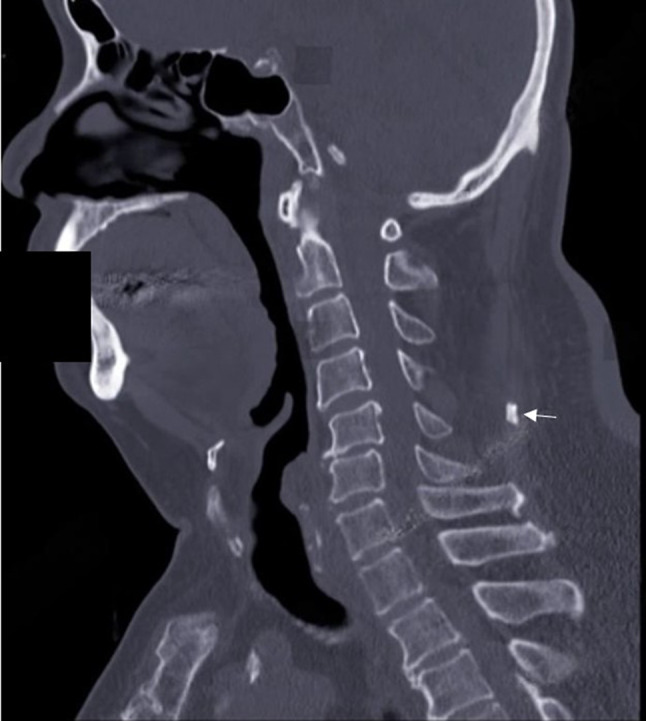

Ossification of Nuchal Ligament (ONL) within the nuchal ligament, which typically remains asymptomatic, is a frequently encountered anatomical variant. The majority of these ossicles exhibit ovoid or round morphology (Fig. 5) [11]. They predominantly manifest at vertebral levels C5-C6 or C6-C7 [11]. Epidemiological considerations indicate their presence in approximately 5.6-7.5% of the population, with a notable male predominance at a ratio of 3:1. The incidence was 11.3% in males and 3.5% in females. The development of these ossicles reaches maturity after the third decade of life [11]. The formation of these ossicles may be attributed to several factors, including a relatively homogeneous patient population, chronic cervical spine overload with age, and the potential influence of cervical motion, particularly hyperflexion of the neck. This motion applies pressure to the nuchal ligament against spinous processes, thereby fostering the development of ossicles in regions of higher mobility [4, 9]. These ossicles are characterized by well-defined, corticated, round, or oval opacities observed on lateral plain radiographs. On CT scans, they manifest as cortical bone with central marrow within the nuchal ligament. It is imperative to distinguish these ossicles from conditions such as myositis ossificans, clay-shoveler fracture, calcareous bursitis, nuchal fibrocartilaginous pseudotumor, heterotrophy in the secondary nucleus of C6, and calcium hydroxyapatite deposition disease [4, 9]. The investigation and understanding of the presence and significance of these additional ossicles are crucial because of their potential association with specific spinal conditions or their ability to induce symptomatic manifestations, necessitating medical evaluation.

Fig. 5.

A sagittal view of a cervical CT scan at the C5-6 level revealed ONL. CT, Computed Tomography, ONL: Ossification of Nuchal Ligament